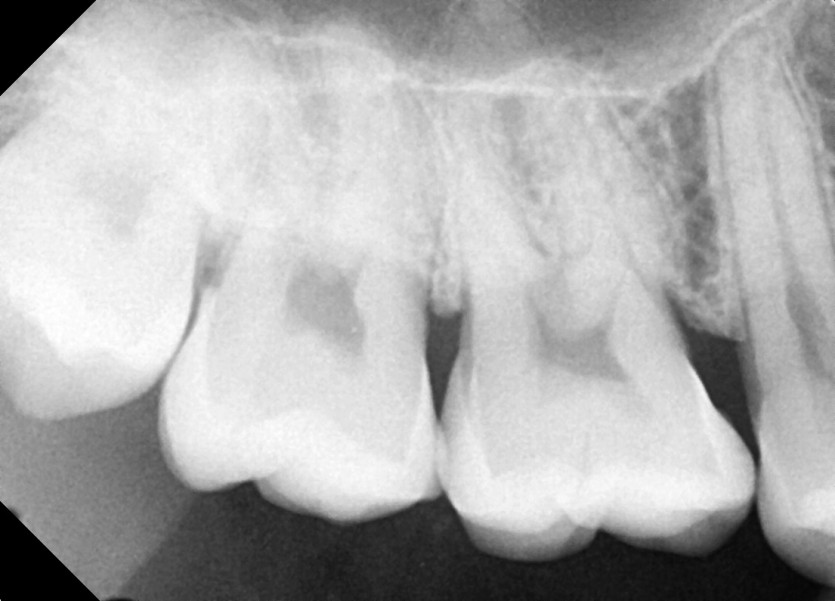

#18,48 사랑니 발치

구강외과 전문의가 당일발치했습니다.